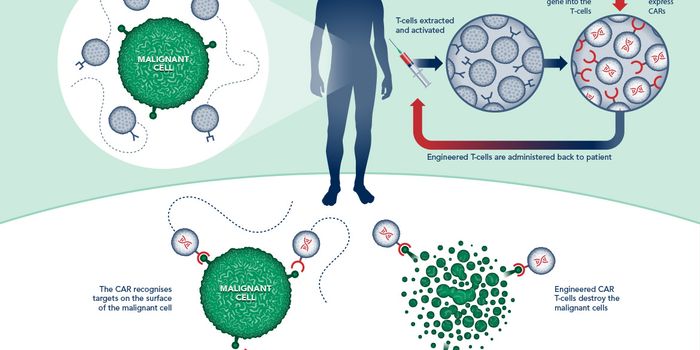

JUN 01, 2016ImmunologyThe 1990s was an exciting time for cancer research, as scientists genetically engineered the very first chimeric antigen ...

MAR 18, 2021Drug Discovery & DevelopmentResearchers have developed a prototype for a new kind of cancer immunotherapy. The therapy uses engineered T-cells to ta ...

JUL 22, 2017CancerA cutting-edge therapy that uses a person’s own immune cells to kill cancer just received a historic vote of confi ...

AUG 01, 2016ImmunologyA new treatment for the selective targeting of ovarian cancer cells has been adopted from chimeric antigen receptor (CAR ...